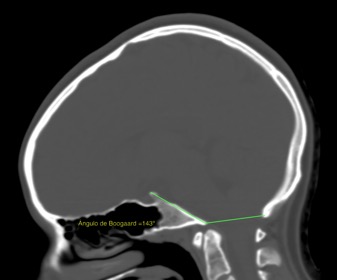

È conosciuta con il nome di Platibasia l’anomalia ossea che consiste nell’appiattimento della base del cranio, che si manifesta nell’apertura dell’angolo di Boogard alla base del cranio. Di norma, il valore di quest’angolo oscilla tra 115° e 140°. Esiste platibasia quando quest’angolo supera i 140°. Inoltre possono essere presi in considerazione altri angoli di riferimento, per esempio quello di Bull (di norma di 13°).

Per la diagnosi e il controllo della Platibasia, si visualizza il cranio con una Tomografia Assiale Computerizzata- TAC del cranio.

Fig. 1 Immagine di Platibasia in una TAC.